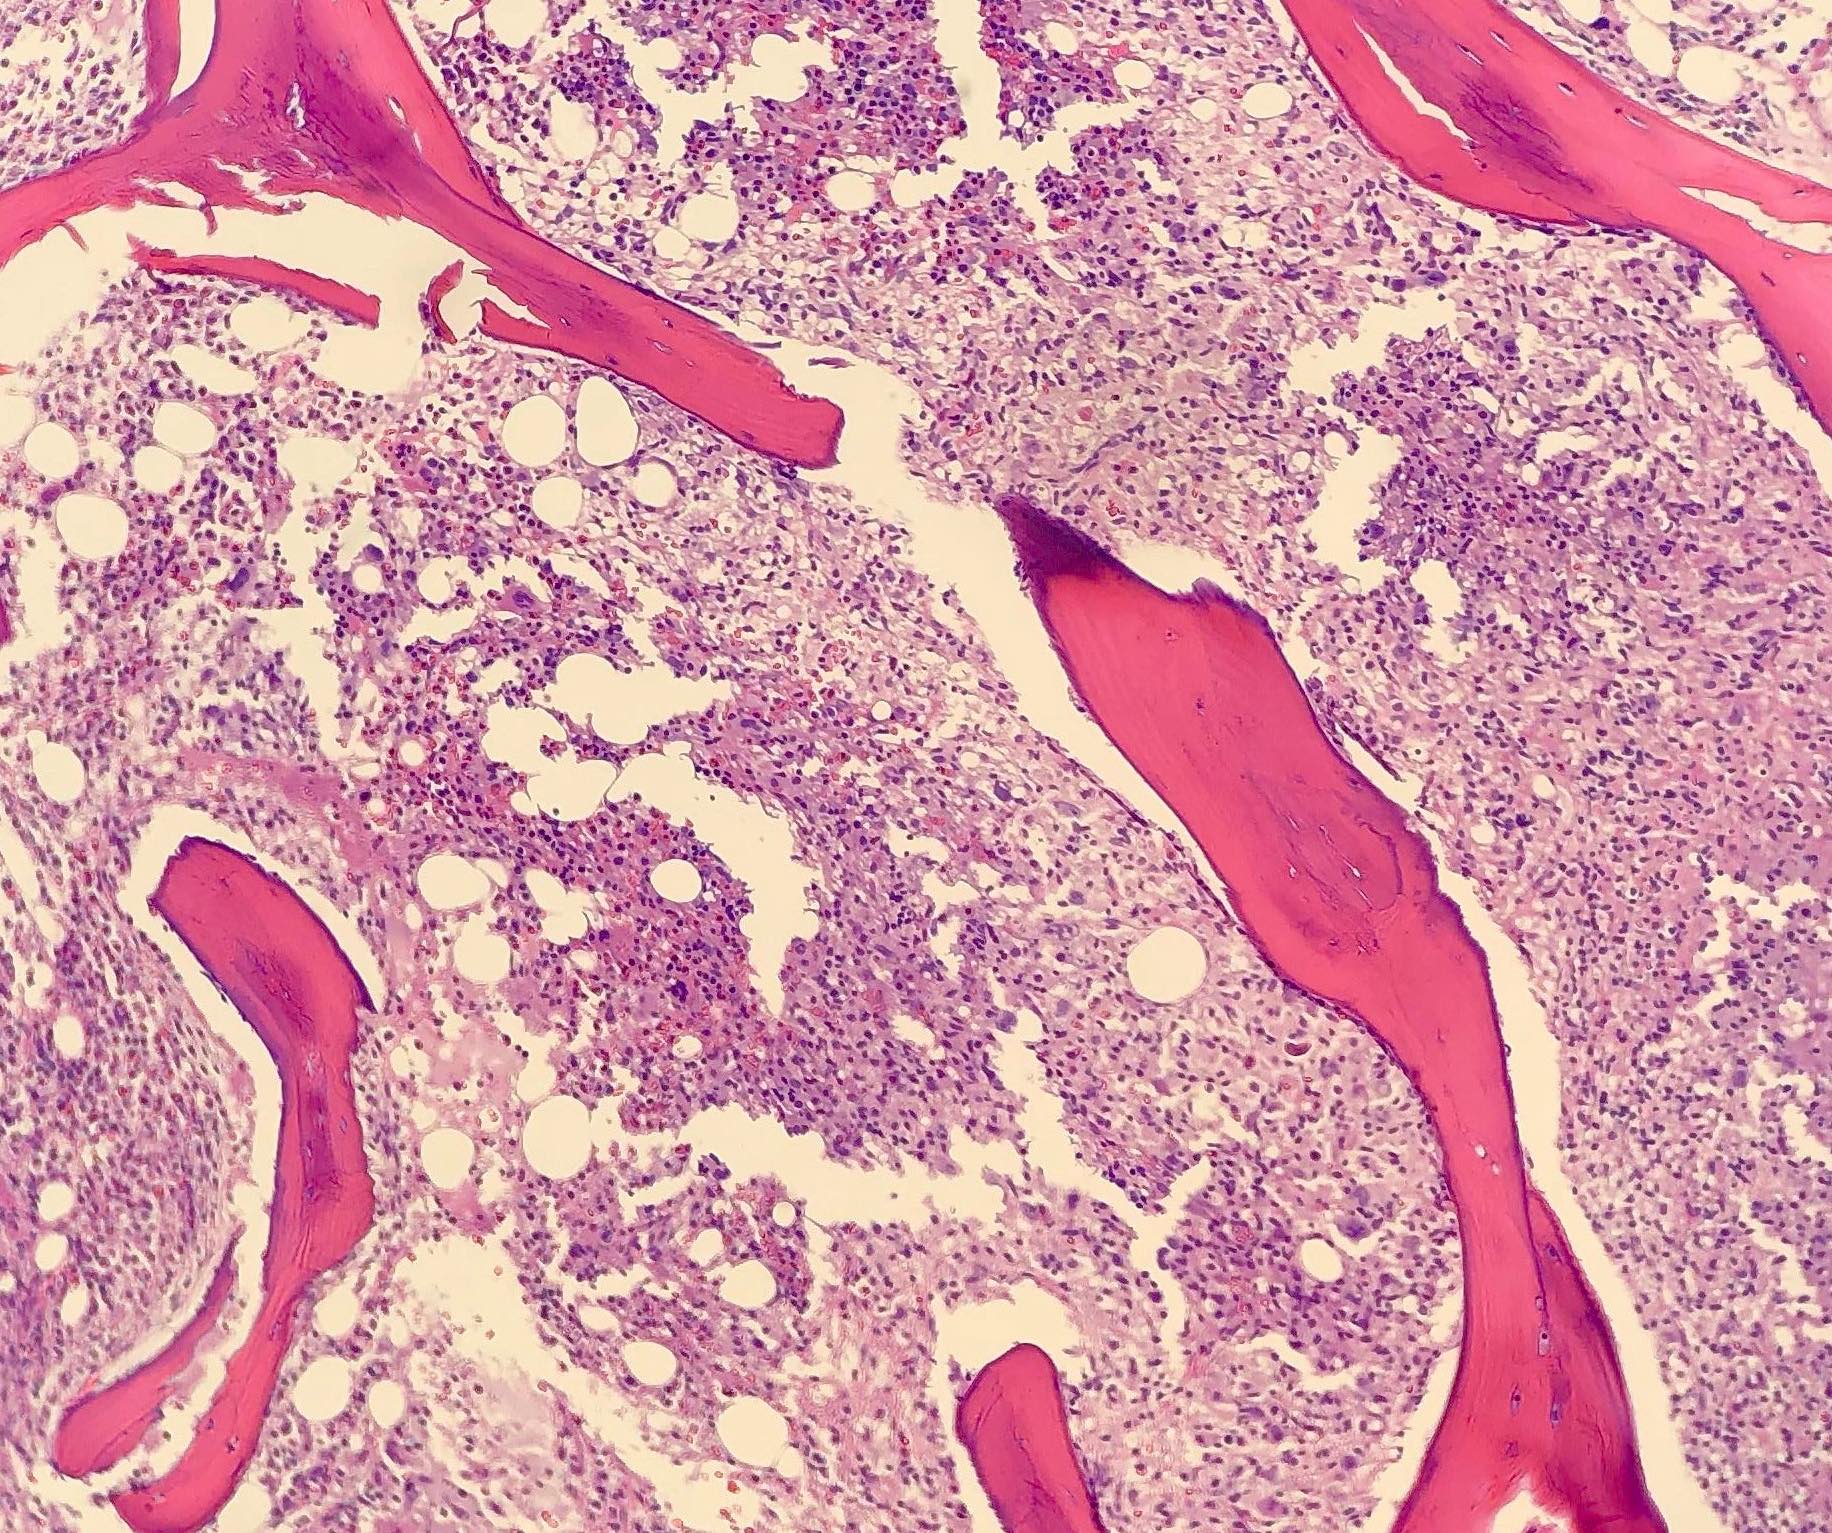

- Bone marrow involvement in 16% (J Clin Oncol 1998;16:2780)

Microscopic (histologic) description

- Partial or complete effacement of normal tissue architecture by a diffuse infiltrate of large (or occasionally medium size) atypical B lymphoid cells with vesicular chromatin and prominent nucleoli

Microscopic (histologic) images